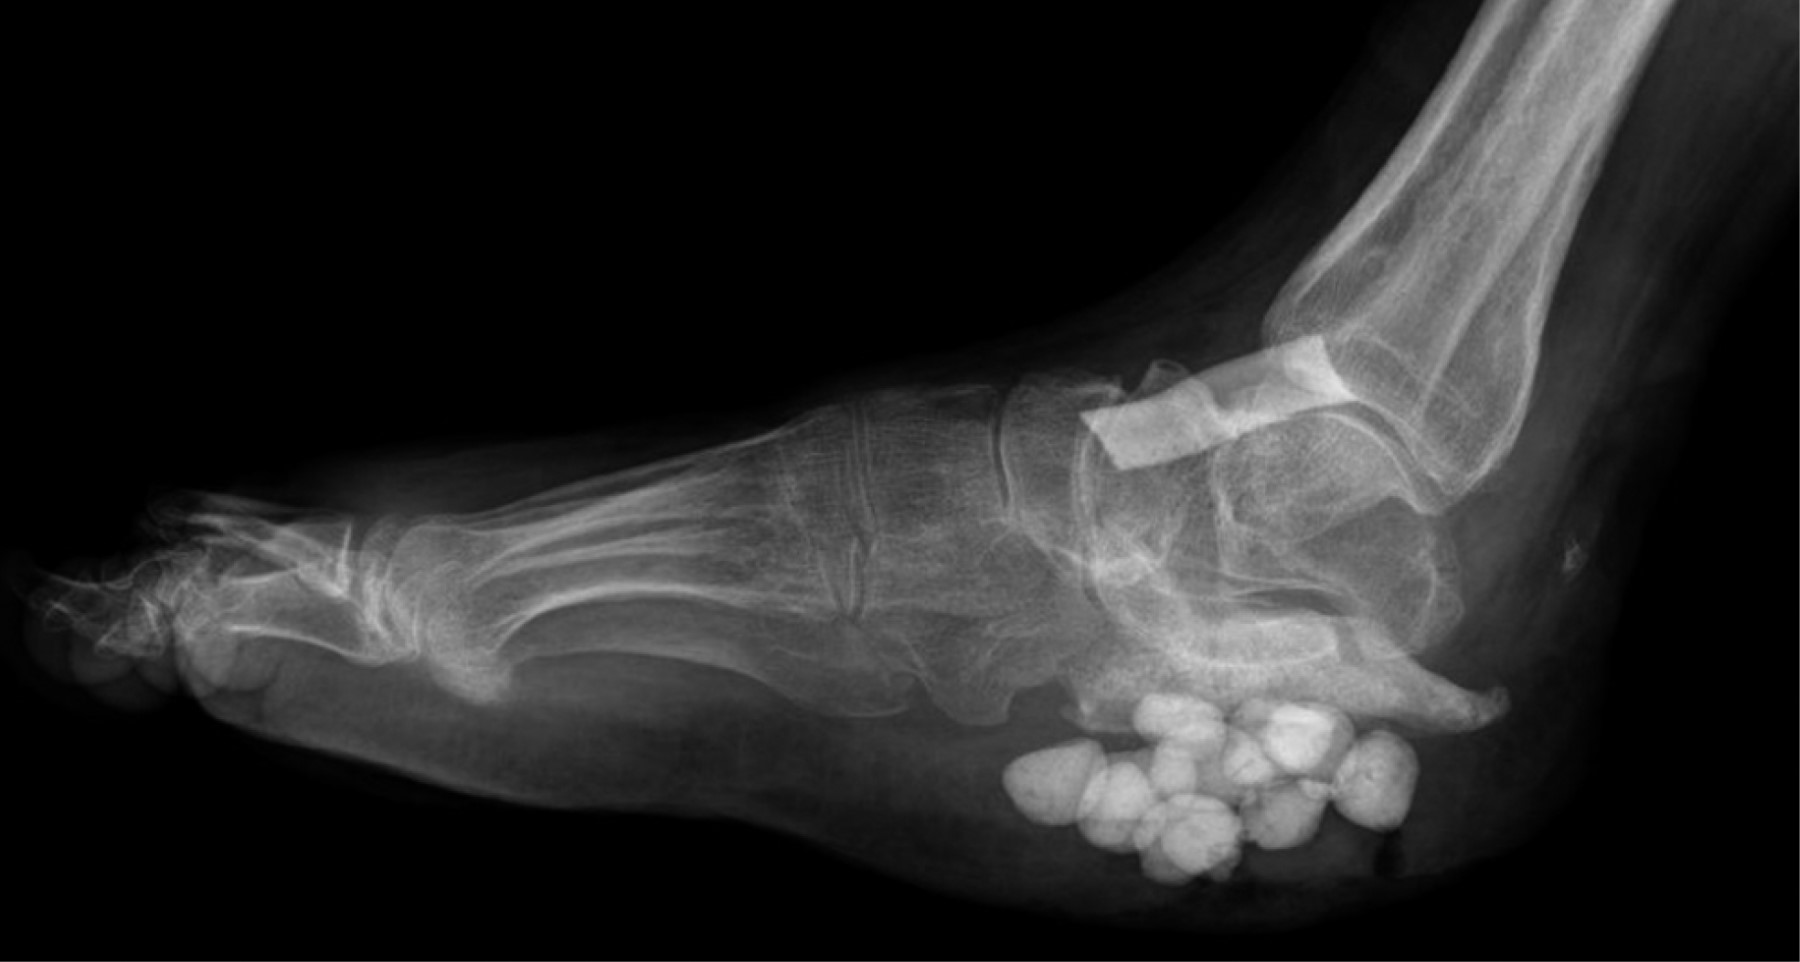

Chronic osteomyelitis of calcaneus: a case report and literature review

We present the case of a 38-year-old male patient at the Miguel Hidalgo Hospital Centenario, Aguascalientes, Mexico, with a five-year history of chronic ulcer on the right heel after direct trauma with a sharp object to the involved heel, with history of flap advancement five years ago. Clinical examination with 7 × 5 cm skin loss with purulent exudate and radiological examination revealed an image of hypotrophy of the right calcaneus with sclerosed bone remains and data suggestive of chronic osteomyelitis. After a first intervention with a polymethylmethacrylate + gentamicin cement spacer with a chain technique and calcaneal curettage, as well as taking a culture, the diagnosis was confirmed with isolation of the Escherichia coli lesion and Enterococcus faecalis, but the spacer was rejected, he intervenes again for calcaneal resection. When the wound heals, ankle foot orthosis is indicated and walking is started without pain, and without recurrence of osteomyelitis.

Figure 3